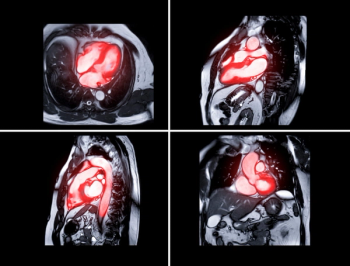

The AI-enabled AutoChamber software also garnered the FDA’s breakthrough device designation for opportunistic detection of enlarged heart chambers on non-contrast CT scans.

The updated software reportedly provides access to more than 200 enhanced features including optimized hanging protocols with a cardiac MRI viewer and perfusion quantification analysis.